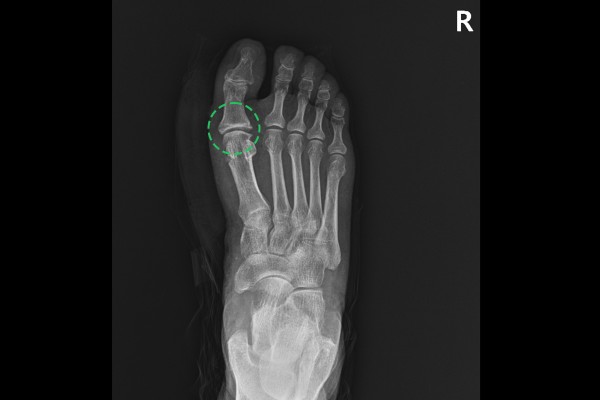

환자분의 발 상태를 확인하기 위해 X-RAY 촬영을 진행하였고, 정상적인 좌측 발과 비교했을 때, 우측 발 엄지 관절이 좁아져 있는 것이 확인되었습니다.